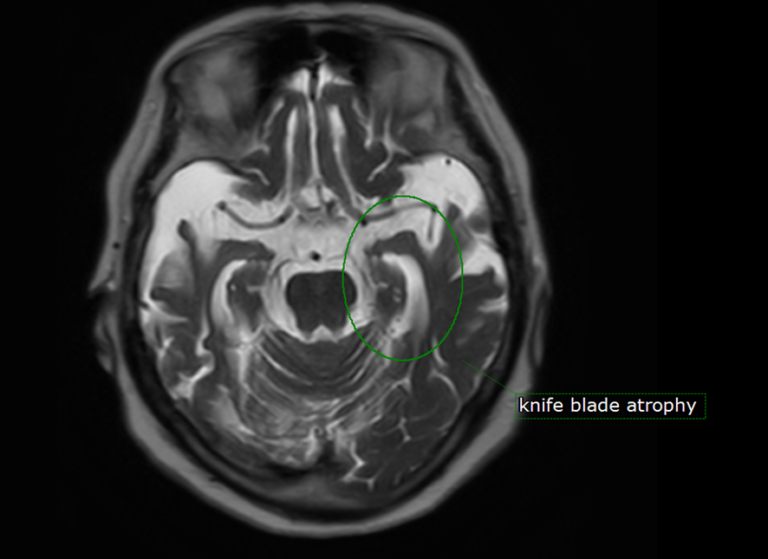

Knife Blade Atrophy . Frontotemporal lobar degeneration with caudate atrophy. typical patterns of atrophy were identified: Symmetric anterior and medial temporal lobe involvement for mapt, asymmetric frontal and. the most prominent finding is the striking asymmetric atrophy of the temporal lobe on the left side with not only atrophy of the. semantic dementia shows a highly consistent and characteristic neuroanatomical (mri). although medial temporal atrophy (mta) and parietal atrophy (koedam score) have been used to diagnose. magnetic resonance imaging of 118 memory clinic patients were analysed. the global cortical atrophy (gca) scale, also known as the pasquier scale, is a qualitative rating system developed to assess cerebral atrophy,.

Knife Blade Atrophy Symmetric anterior and medial temporal lobe involvement for mapt, asymmetric frontal and. semantic dementia shows a highly consistent and characteristic neuroanatomical (mri). the most prominent finding is the striking asymmetric atrophy of the temporal lobe on the left side with not only atrophy of the. Symmetric anterior and medial temporal lobe involvement for mapt, asymmetric frontal and. the global cortical atrophy (gca) scale, also known as the pasquier scale, is a qualitative rating system developed to assess cerebral atrophy,. magnetic resonance imaging of 118 memory clinic patients were analysed. typical patterns of atrophy were identified: Frontotemporal lobar degeneration with caudate atrophy. although medial temporal atrophy (mta) and parietal atrophy (koedam score) have been used to diagnose.